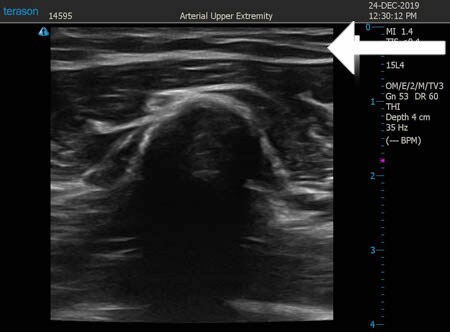

同様に左二の腕 ↓ ↓ ↓

↓ ↓ ↓

左ちからこぶ